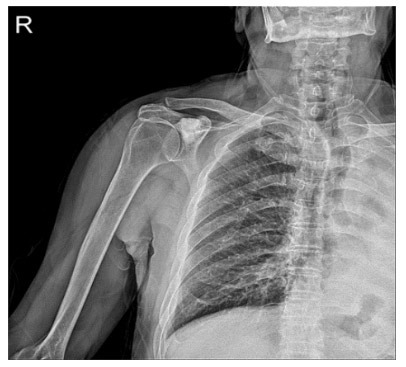

Post-surgery: The X-ray shows that the cavity created after tumor removal has been filled with bone cement.